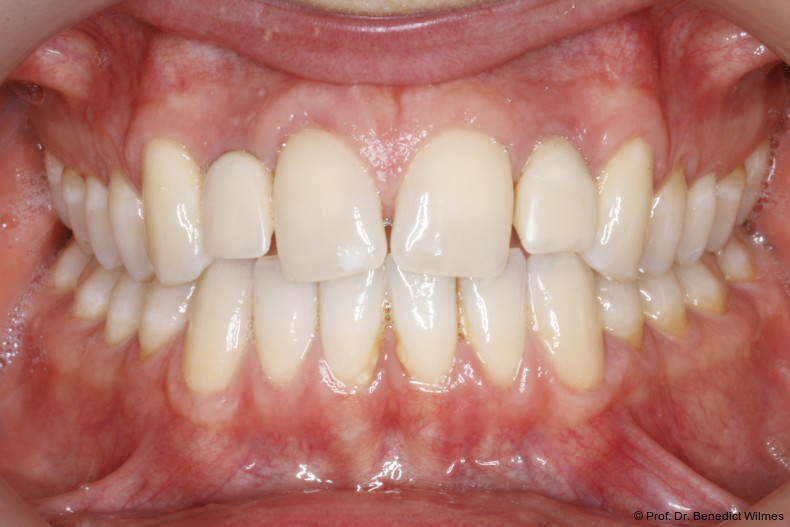

Ein 14-jähriger Patient wurde bei Aplasie der beiden oberen seitlichen Schneidezähne mit dem Ziel der beidseitigen Lückenöffnung kieferorthopädisch therapiert (Abb. 1a+b). Zum Ende der kieferorthopädischen Behandlung wurden zwei Miniimplantate in Regio 2er als temporärer Zahnersatz inseriert (Benefit System, PSM, 2 x 13 mm, Abb. 2a+b). Nach Abdrucknahme wurden Kronen auf den Peek-Abutments modelliert und diese mit Kunststoff auf die Abutments geklebt (Abb. 3a–d). In den Abbildungen 3 und 4 sind die klinischen und röntgenologischen Nachkontrollen innerhalb der nächsten achteinhalb Jahre dokumentiert. Man erkennt einen sowohl in der Höhe als auch in bukkopalatinalen Breite verbleibenden gesunden Knochen ohne Anzeichen einer Atrophie. Im Alter von 23 Jahren wurden die definitiven Implantate ohne die Notwendigkeit einer Augmentation eingesetzt (Abb. 5) und nach Einheilung prothetisch versorgt (Abb. 6a–e und Abb. 7a–c).